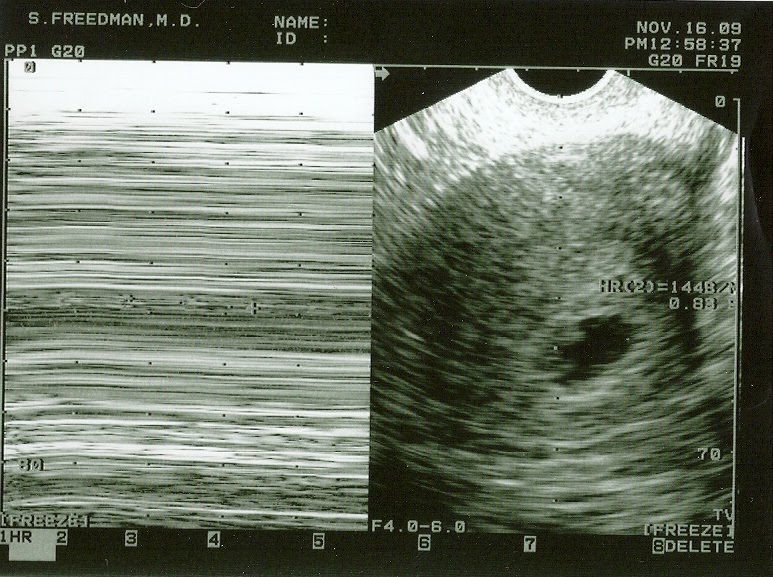

I am officially 19 weeks today! Can you believe it? While I realize that I am probably the only one keeping track at the moment, its still unbelievable! I know I haven’t posted much about our new addition to the family, there hasn’t been much to tell. Our first ultrasound, taken at 6 weeks and 6 days gave us the first glimpse of our little one. In the picture below you can just make out the little kidney bean shape on the left hand side, which is our little Marshmallow. I will say it took forever to find him/her… only 6 weeks old and already moving around enough to hide from everyone!

At about 10 weeks my OB did another ultrasound, but unfortunatly there were a few issues with the printer. Thats ok though, there is one on my file that she says I can have. At 10 weeks, the baby was starting to take more of a form… a little kidney bean with flippers for feet. Once again, he/she was hard to find at first and during the ultrasound continued to move and made things a little difficult for my OB. Funny… Abby was the same way! Since my 10 week appointment we have been able to hear the heartbeat each time I have gone in and everything sounds great!